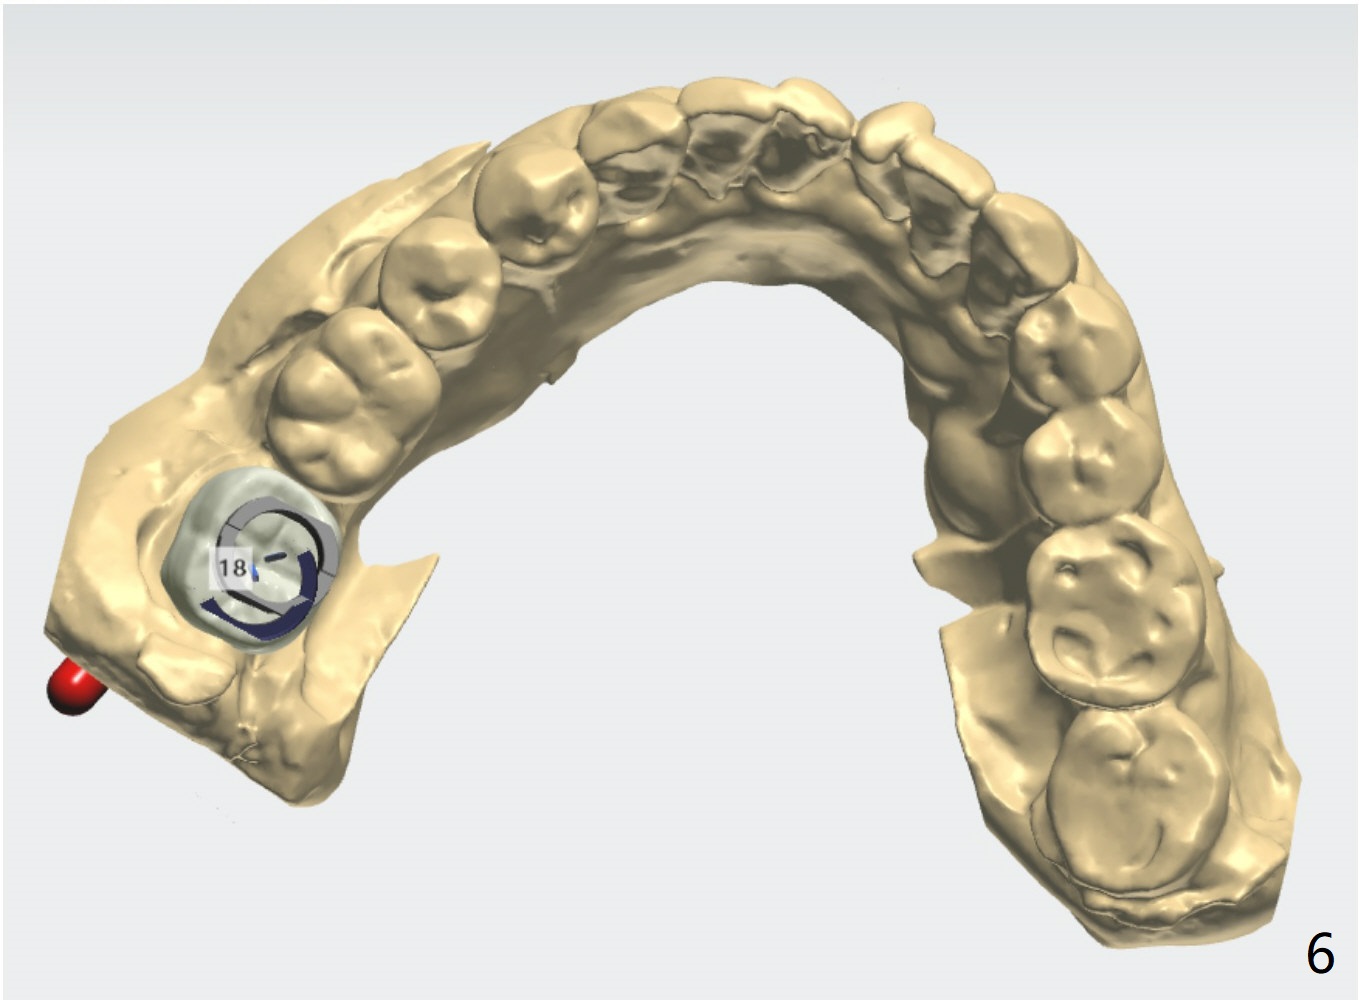

Short Implants

A 73-year-old woman

Xin Wei, DDS, PhD, MS 1st edition 03/15/2021, last revision 04/10/2021